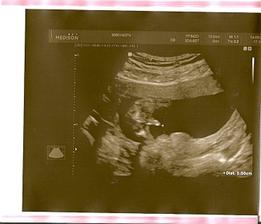

Pořídíme Míše Ríšu 🙂

tak se nám zadařilo počít sourozence, opět to byl fofr, první měsíc, takže opět trochu šok i když příjemný

zatím všechno vypadá krásně, mamince je dobře, doktoři jí hlídají na všech frontách, tak snad se nám tentokrát podaří dočkat se termínu 22.2.2011 🙂